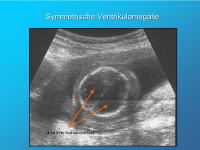

Symmetrische Ventrikulomegalie

Abbildung 6

Keywords:

Seitenventrikel

Ventrikulomegalie